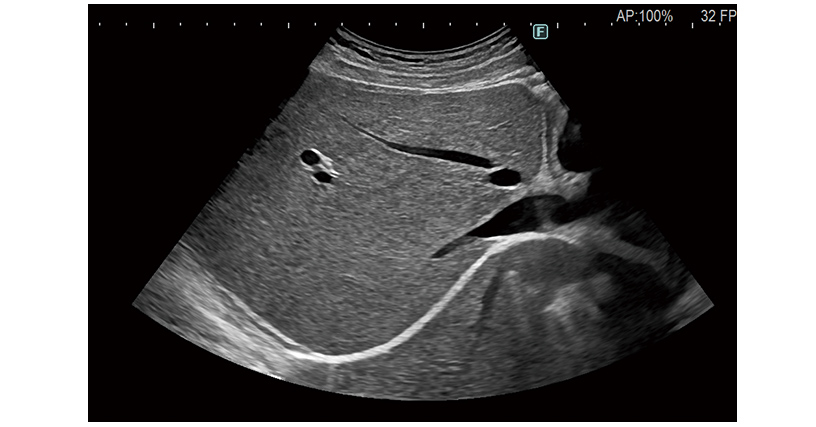

Mit der Ultraschallbildgebung sind jetzt eine höhere Untersuchungsgenauigkeit, mehr Komfort und ein breiteres Anwendungsspektrum möglich.

Die ARIETTA 850 DeepInsight kann flexibel auf die individuellen Bedürfnisse der Anwender in den verschiedenen klinischen Disziplinen reagieren und bietet diagnostische Bildgebung ohne Kompromisse.